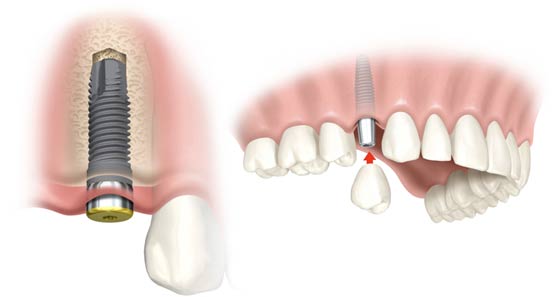

- Implantati se hirurški ugrađuju u kost. Postupak je brzo gotov i bezbolan, budući da se izvodi pod lokalnom anestezijom. Nakon ugradnje implant srasta sa kosti - “osteointegracija“ , što obično traje 2 do 6 meseci.

- Nakon ovog perioda na implant se postavlja nadgradnja (suprastruktura) na koju ide protetska krunica ili neko drugo protetsko resenje u zavisnosti od plana terapija.

- Kada nedostaje jedan ili vise zuba